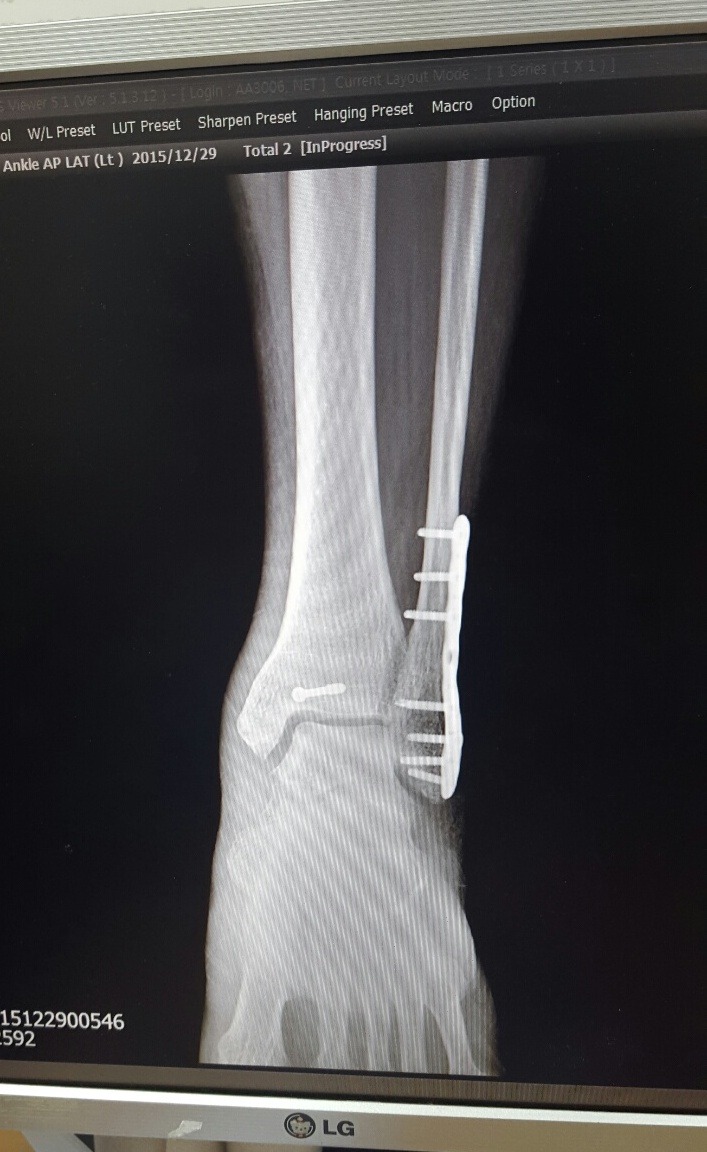

2015년 12월 29일(화)

역시 사진 먼저찍고 기다리다 순번에따라 진료실에 들어갔더니

골진이 많이 나와서 뼈가 잘 붙어가고있다는 희망적인 말을 듣게 되었고

이제부터 체중을 싣고 걸음연습을 하라고했다. 날아갈 듯 기뻤다.

회복속도가 엄청 빠르다는 이야기.